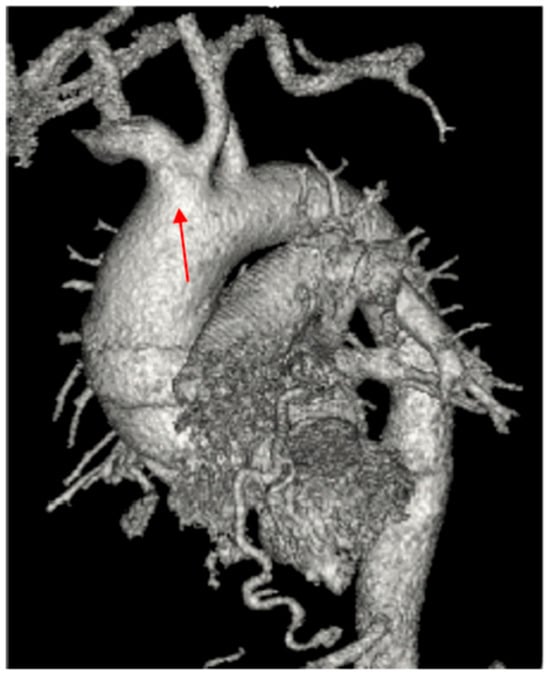

Management of a Rare Case of Multiple Coronary Artery Fistulas Associated with Ascending Aortic and Root Aneurysm: Case Report and Review of Literature

2. Case Report